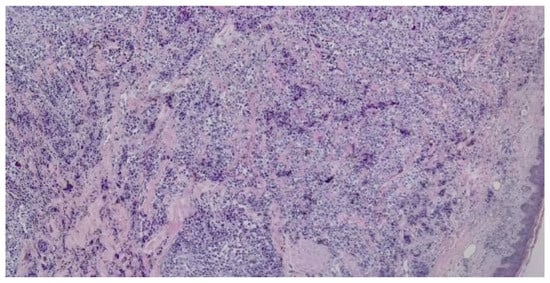

Based on the initial skin examination, a presumptive diagnosis of infected Kaposi's sarcoma was made. However, the unusual, extensive presentation prompted additional investigations. An excisional biopsy of an isolated lesion was performed to confirm the diagnosis (Figure 3 and Figure 4). The biopsy ruled out Kaposi's sarcoma and revealed the following: moderate orthokeratosis at the epidermal level, with focal pigmentation of the basal layer, and a densely cellular intradermal tumoral proliferation composed of medium to large-sized cells with abundant, frequently retracted cytoplasm. Some cells appeared ballooned, with large, prominent eosinophilic nucleoli, arranged in nests and interconnected clusters with an alveolar pattern, separated by connective-vascular septa. There was occasional discrete deposition of brown pigment, with invasion into the hypodermis, in contact with the deep excision margin. The mitotic index was less than 1/mm². Lymphatic invasion was present. There was a focal, minimal, discontinuous peritumoral lymphomononuclear inflammatory infiltrate, with limited areas of segmental tumor regression, moderate fibrosis, rare lymphocytes, and telangiectasias. These histopathological features were consistent with nodular malignant melanoma, Clark level V, with extensive involvement of the hypodermis and lymphatic spread. The biopsy specimen was sent for immunohistochemical analysis, which confirmed the diagnosis of malignant melanoma.

Figure 3. Dense intradermal proliferation with the formation of nests, clusters, and cords with uneven pigmentation (haematoxilin and eosin staining, 5x).